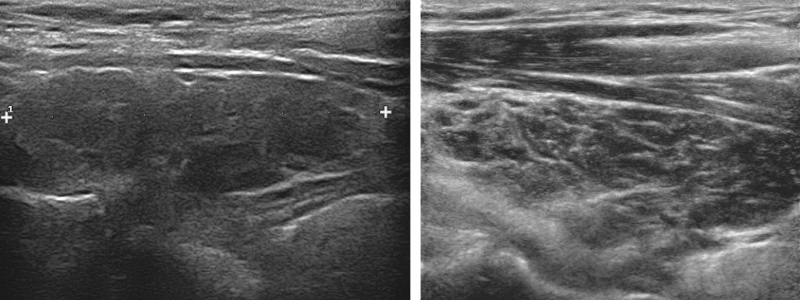

- goitre hypoéchogène micronodulaire, Ac anti-TPO +/- anti-Tg

- hypervascularisation modérée < 1 m/s

- suivi/an, travées fibreuses hyperécho, /!\ lymphome/cancer